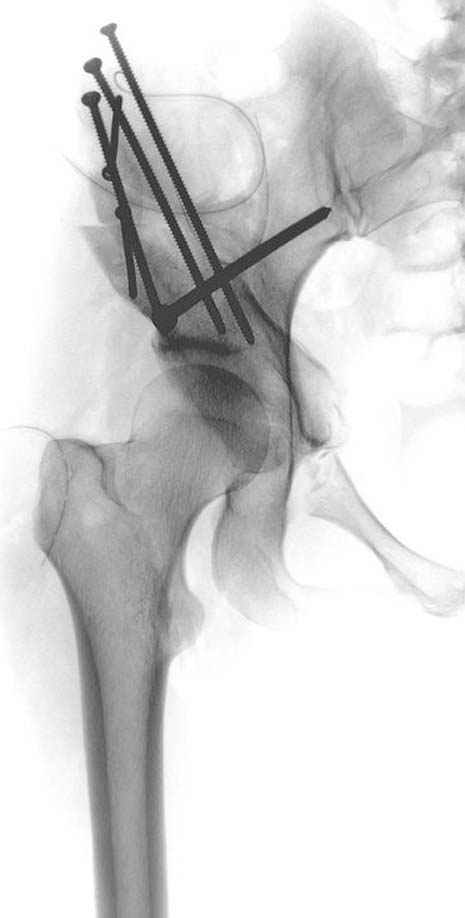

Рис.2 Та же трехмерная модель тазобедренного сустава без аналога связки головки бедра. Пружина динамометра удерживает тазовую часть модели от опрокидывания, поддерживая стабильность так же, как отводящие мышцы обеспечивают ее в отсутствии связки головки бедра.